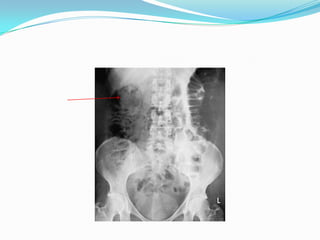

Plain radiograph

 In severe disease, the luminal margin of the colon becomes

edematous and irregular.

 Thickening of the colonic wall often is apparent on a plain film

 Plain films also are useful for detecting the presence of fecal

material.

 The presence of marked colonic dilatation suggests fulminant

colitis or toxic megacolon.

Toxic megacolon